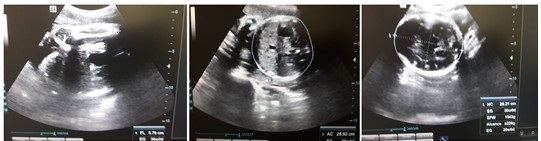

La gestación que la trajo en un segundo momento a los servicios obstétricos, constituyó un resultado importante. Se consideró como de alto riesgo obstétrico, y se realizaron orientaciones específicas para el seguimiento en la atención prenatal, al existir altas probabilidades de morbimortalidad perinatal. La evolución clínica ha sido favorable hasta el tercer trimestre, sin patologías propias o asociadas al embarazo, y con curvas de peso, tensión arterial y de altura uterina acordes al período de gravidez. Se realizó ecografía obstétrica correspondiente al período gestacional, que confirmó el completo bienestar materno fetal. (Figura 3).